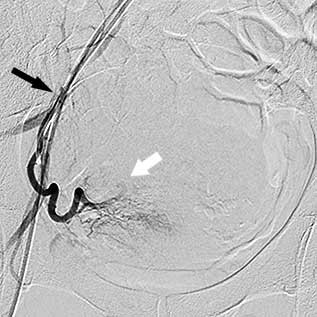

міома матки після емболізації    міома матки після емболізації

Катетер у правій матковій артерії

(чорна стрілка), вузлові артерії

не контрастуються

Катетер у лівій матковій артерії

Прокол шкіри, через який вводився катетер, оброблюють та закривають стерильною компресійною пов’язкою на 12 годин. У результаті обмеження кровопостачання пухлина (або пухлини) починає зменшуватись у розмірах. Емболізація маткових артерій зазвичай потребує перебування в лікарні протягом 1-3 діб. Після процедури необхідний постільний режим протягом 6–8 годин. У післяопераційний період призначаються знеболювальні препарати для боротьби з больовим синдромом, який з тією чи іншою інтенсивністю виникає в усіх пацієнток. Крім того, можливе підвищення температури. У такому випадку додатково призначаються протизапальні засоби. Повне відновлення зазвичай займає близько 2 тижнів, однак цей термін може мінятися залежно від розміру та кількості вузлів.